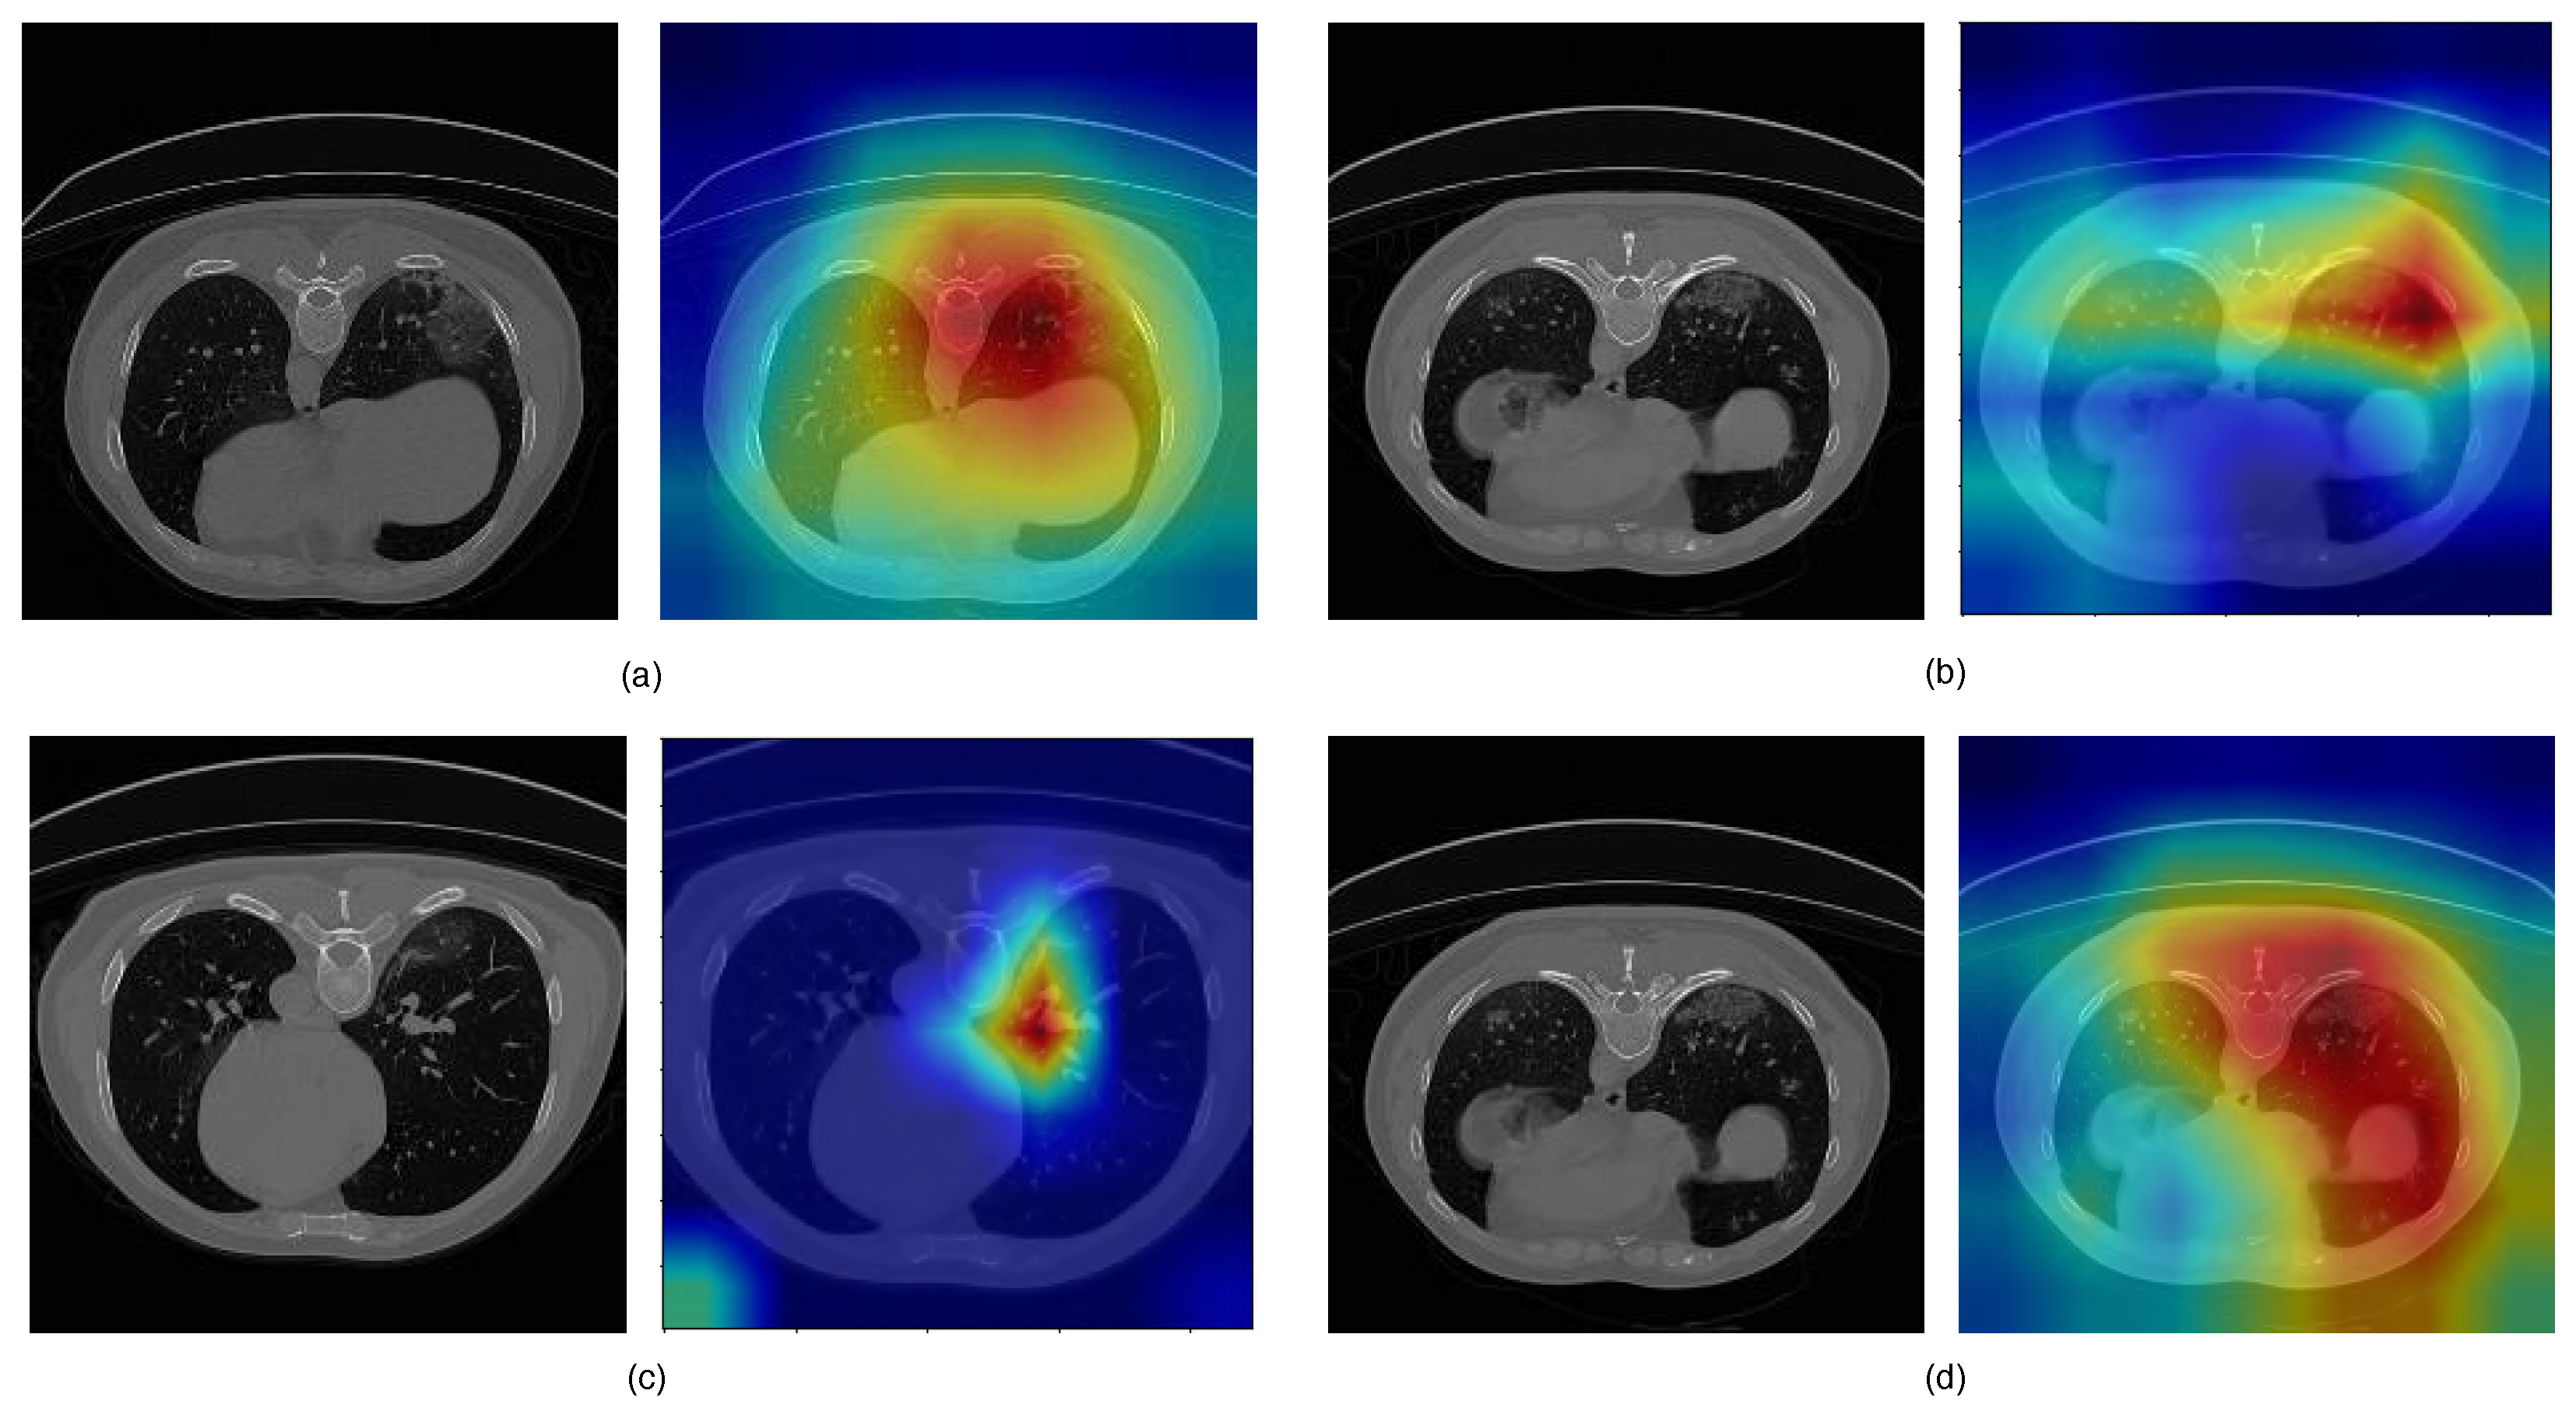

Feature Attention Module (FAM)

3.3. Analysis of the Performance of the Proposed Model